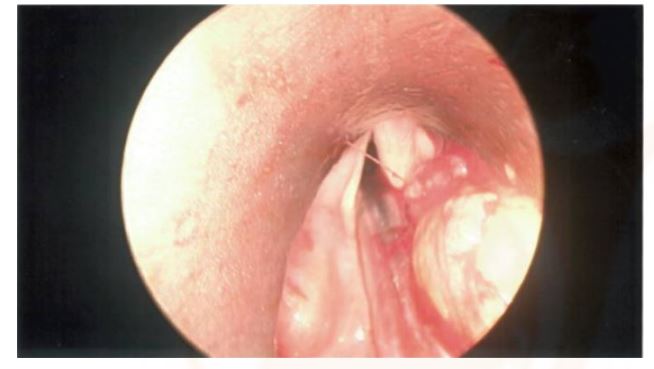

In November 2023, the patient underwent orotracheal intubation and endoscopic excision of the mass via microlaryngoscopy under general anaesthesia with a stepwise approach (see Figures 2A, 2C & 2D).The true and false vocal cords were fully visualised and seen to be healthy (see Figure 2B).The fatty mass was nearly completely resected using a cold steel technique assisted by endoscopy. Minimal bleeding was observed during the operation and no postoperative complications occurred.